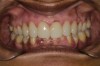

Fig 1. Preoperative frontal smile view.

Figure 1

A 40-year-old female patient complained of short teeth and asked for various options to improve her smile. On clinical examination, the palatal surfaces of the maxillary anterior teeth were found to be eroded, with the residual tooth structure having a smooth and shiny appearance (Figure 1 through Figure 3). In MIP, no restorative space was available, as the lower anterior teeth fit tightly into the upper palatal surfaces, making this a clinically challenging situation to treat conservatively. In most cases of conventional treatment protocols, such upper teeth are devitalized and restored with crowns that structurally leave the teeth in a compromised condition.10